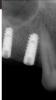

dantists Опубликовано 23 марта, 2008 Автор Поделиться Опубликовано 23 марта, 2008 мне кажется что это надо что-то другое попоробовать. язык всегда во вредные места лезет. хочет узелки пощупать,а там итак всё в натяжку. разве что капу защитную делать.вот другой пациент вот другой пациентподскажите в чём проблема. Ссылка на комментарий

Bier Опубликовано 23 марта, 2008 Поделиться Опубликовано 23 марта, 2008 на первом снимке - вы поставили имплантат в периодонт, отсюда и проблемы. На втором резьба у имплантатов не оголена, кстати на мой взгляд имплантаты в позициях 15-16 очень близко друг к другу. Есть ли там 3 мм? Ссылка на комментарий

dantists Опубликовано 23 марта, 2008 Автор Поделиться Опубликовано 23 марта, 2008 на первом снимке - вы поставили имплантат в периодонт, отсюда и проблемы. На втором резьба у имплантатов не оголена, кстати на мой взгляд имплантаты в позициях 15-16 очень близко друг к другу. Есть ли там 3 мм?но тут не в близкости дело,тут что-то другое. голову ломаю и ничего не приходит. сейчас кстати мировая тенденция 2мм. вот снимок как было на первом снимке - вы поставили имплантат в периодонт, отсюда и проблемы. На втором резьба у имплантатов не оголена, кстати на мой взгляд имплантаты в позициях 15-16 очень близко друг к другу. Есть ли там 3 мм?но тут не в близкости дело,тут что-то другое. голову ломаю и ничего не приходит. сейчас кстати мировая тенденция 2мм. вот снимок как было Ссылка на комментарий

Bier Опубликовано 24 марта, 2008 Поделиться Опубликовано 24 марта, 2008 может быть дело в гладкой шейке? Ссылка на комментарий

dantists Опубликовано 25 марта, 2008 Автор Поделиться Опубликовано 25 марта, 2008 может быть дело в гладкой шейке?там один милиметр гладкой шейки. а резорбции 2мм. импланты остеоинтегрированные. я тоже об этом думал. Ссылка на комментарий